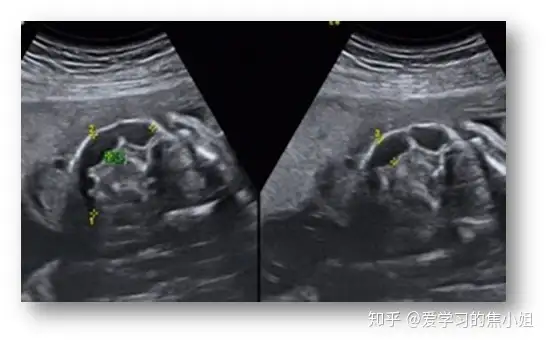

五、侧脑室增宽(VM)

侧脑室位于大脑半球的深部,左、右各一,呈“C”形室腔,内衬室管膜,腔内充满脑脊液。分为中央部、前角、后角、下角,并以室间孔与第三脑室相通。

正常:侧脑室体部宽度≤10mm,平均7mm。

侧脑室扩大:直径10mm以上。轻度脑室扩大(MVM)定义为10至15毫米之间。常有胎儿脑积水的表现。

脑积水:指伴有脑脊液压力增加的侧脑室增宽者,常伴有头围异常。分为梗阻性脑积水和交通性脑积水。VM原因:脑脊液回流异常、神经元移行障碍、破坏性进程。重度的侧脑室增宽可有脑脊液动力改变、脑组织结构异常和脑组织破坏。